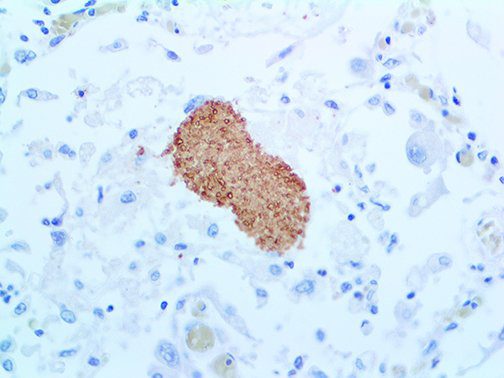

It is the ICU physician who is most likely to witness one of the deadliest manifestations of the abnormal immunological response, the cytokine storm syndrome (CSS). This response is also referred to by some as the cytokine release syndrome (CRS). CSS is characterized by continuous activation and expansion of macrophage and lymphocyte populations, which secrete large amounts of cytokines, causing the cytokine storm. This massive cytokine release is akin to hemophagocytic lymphohistiocytosis (HLH) disease, a syndrome characterized by initial unchecked and persistent activation of cytotoxic T lymphocytes and NK cells.

Clinical and laboratory manifestations of HLH include fever, enlarged liver and/or spleen, neurologic dysfunction, coagulopathy, liver dysfunction, cytopenias (i.e., low levels of erythrocytes, leukocytes, and/or platelets), hypertriglyceridemia, hyperferritinemia, hemophagocytosis, and eventually diminished NK cell activity as the immune system becomes progressively paralyzed. HLH can be familial (primary HLH) or secondary to another disease process (sHLH), such as rheumatic disease, in which it is referred to as macrophage activation syndrome (MAS, characterized by elevated ferritin).